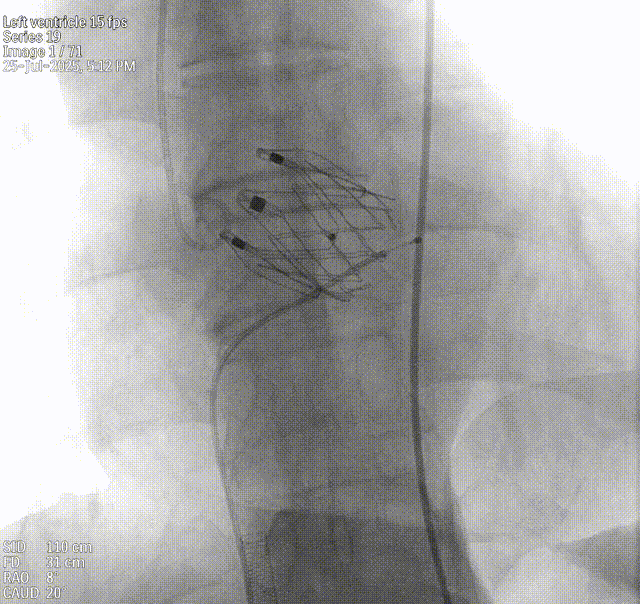

术中回顾及效果

手术过程顺利。术中通过右窦居中造影、定位件入窦造影及释放后功能确认等关键步骤,确保瓣膜锚定准确。器械用时仅10分钟。术后患者主动脉瓣重度反流纠正,无反流、无瓣周漏。心脏彩超显示人工生物瓣启闭良好,平均跨瓣压差4mmHg,流速正常。患者恢复情况良好,心脏功能得到显著改善。

术后造影